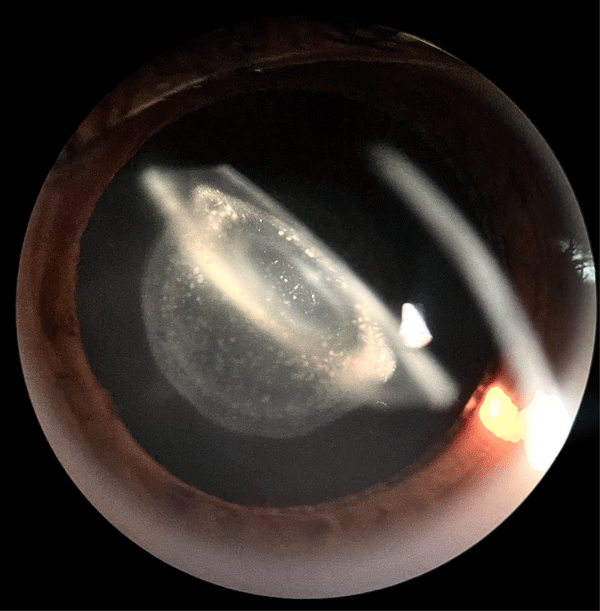

Se presenta el caso de una paciente femenina de 13 años que consultó por disminución de la agudeza visual bilateral, con una agudeza visual inicial de 1/10 en ambos ojos mejor corregida. En los estudios preoperatorios se constató la presencia de un astigmatismo elevado, de 3 dioptrías en ambos ojos, asociado a una opacidad congénita del cristalino con un patrón anular que recuerda la estructura de los anillos de Saturno.

Se decidió realizar la cirugía de catarata bilateral con implante de lente intraocular monofocal tórico y se obtuvo un resultado visual postoperatorio de 10/10 sin corrección a distancia en ambos ojos.

Esta imagen ilustra una forma rara y visualmente llamativa de catarata congénita en la que la disposición concéntrica de las opacidades ofrece un interés tanto clínico como estético. Su documentación contribuye al conocimiento de las variaciones morfológicas de las cataratas congénitas y resalta la importancia del examen detallado previo a la cirugía para la elección personalizada de la lente intraocular.

A case is presented of a 13-year-old female patient who attended consultation for decreased bilateral visual acuity, with an initial visual acuity of 1/10 in both eyes. Preoperative studies revealed high astigmatism associated with a congenital lens opacity showing an annular pattern resembling the rings of Saturn.

Bilateral cataract surgery was performed with implantation of monofocal toric intraocular lenses, achieving a postoperative uncorrected distance visual acuity of 10/10 in both eyes.

This image illustrates a rare and visually striking form of congenital cataract, in which the concentric arrangement of opacities offers both clinical and aesthetic interest. Its documentation contributes to understanding the morphological variability of congenital cataracts and highlights the importance of detailed preoperative assessment for personalized intraocular lens selection.